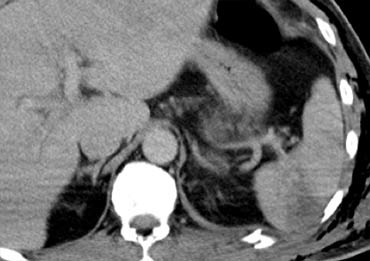

Bên trái là hai ví dụ khác về đường rách gan.

Các đường rách có thể có hình sao, như ví dụ bên trái, hoặc hình phân nhánh như ví dụ bên phải.